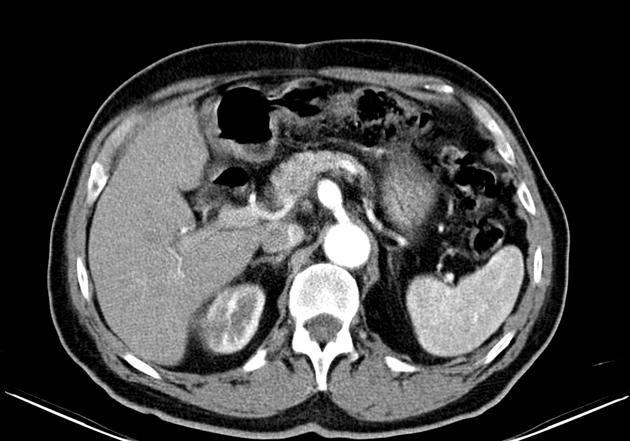

At the core of this discussion is a poignant case report detailing the treatment of a patient with a ruptured celiac artery aneurysm. Despite representing one of the rarer types of visceral artery aneurysms, the risk of rupture—ranging between 10% and 20% in the literature—is a scary reminder of the many twisted issues that surgeons need to resolve in high-pressure situations.

A celiac artery aneurysm involves a localized ballooning or bulging in the wall of the celiac artery, a key blood vessel supplying oxygenated blood to the upper abdominal organs. Patients may remain asymptomatic for long periods, with diagnosis often occurring when the aneurysm has already ruptured. Given the subtle symptoms and the hidden complexities of the condition, early detection remains a significant challenge.

Scientific observations have identified that although CAAs are the fourth most common among visceral artery aneurysms, the risk of rupture is not negligible. With rupture figures reported between 10% and 20%, the complications are intimidating due to their potential for massive internal bleeding and subsequent multiple organ failure. This underscores the pressing need for both early diagnosis and effective treatment strategies.